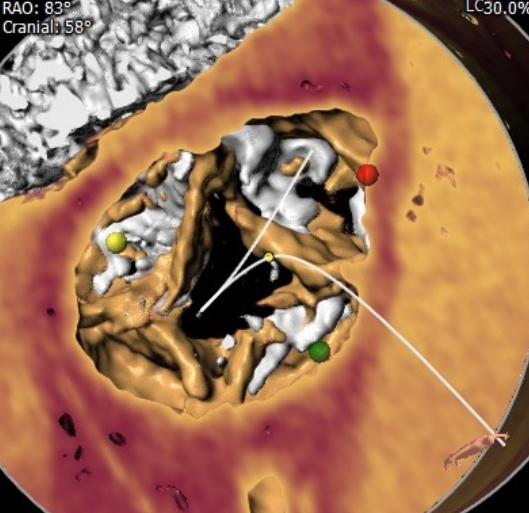

患者入路良好,无迂曲、无钙化,直径大于5.0mm;由于为重度钙化Type0型二叶瓣,瓣叶交界处有巨大钙化结节,预计不可移动,为避免根部夹层,因此需考虑Downsize策略;升主增宽,选择球扩瓣可调弯系统可减少对主动脉弓的损伤,增强通过性。拟全麻,以右股为主入路,20mm球囊预扩张推挤钙化,备选23mm SAPIEN 3瓣膜,植入高度90/10。

手术过程

全麻下建立双侧股动脉入路,以右股动脉为主;导丝跨瓣后置换猪尾导管,确定共平面。

图片

使用20mm球囊进行预扩,无腰征无反流。

预扩未见右冠显影,球囊主动保护。

通过支撑导丝,送入23mm SAPIEN 3瓣膜,使用独特调弯功能,保证安全过弓并成功跨瓣;调整至共平面角度,瓣膜到位,快速起搏下+1cc精准释放瓣膜。

撤出导丝后,造影超声结果均显示瓣膜工作良好,瓣膜释放后流入/流出比例=90 :10,术后导管测量压差6mmHg,经胸超声检测微量瓣周漏,无冠脉阻塞、无支架植入、无起搏器植入、无并发症,手术成功。